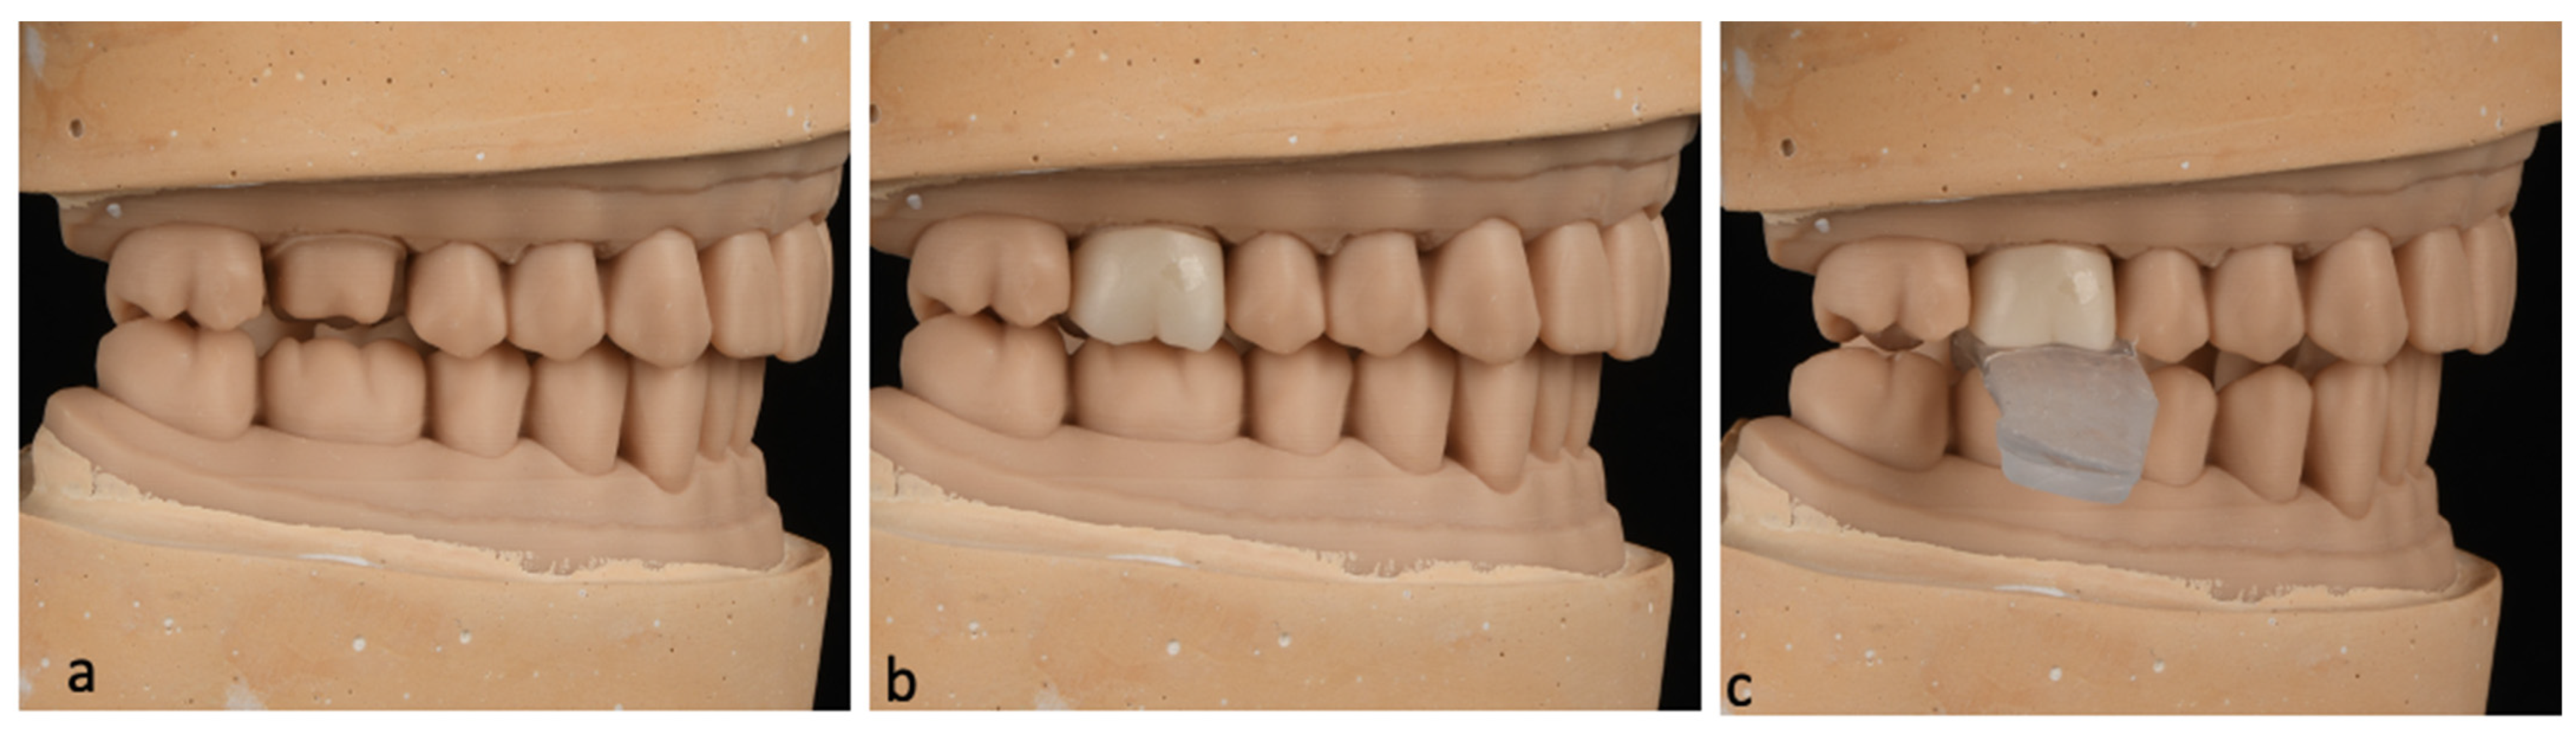

Prior to the cementation of each sample, adjustments in the interproximal and occlusal contacts were made to confirm the fit and seat of the crown on the cast and maintain the existing occlusion at MIP. Following the adjustments, a crown insertion guide was made for each sample using thermoplastic material that was heat-molded onto the occlusal surface while the crown was held under a 5 kg static load to ensure correct insertion orientation during cementation and simulate the insertion process in a clinical setting (

Figure 1).